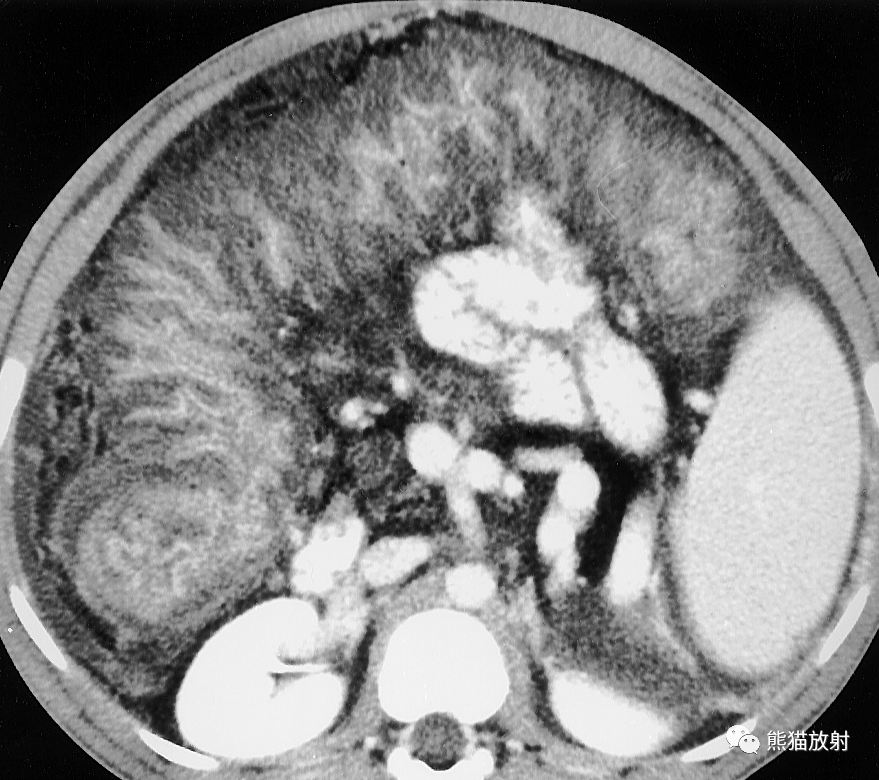

克罗恩病。使用口服和静脉造影剂获得的CT扫描显示脓肿累及髂肌(黑箭),与前腹壁间可见瘘管(白箭)。